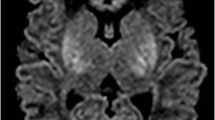

Early visual analysis may be particularly misleading when there has been widespread injury to the WM and BGT, probably because there is no normal tissue for comparison (Fig. 7). A visual clue may be found by observing the appearance of the usually normal-appearing cerebellum (Fig. 11). In these infants, measuring the ADC values will correctly detect the presence of ischaemic tissue. Worrying, however, is that both the early visual appearances of DWI and the ADC values may be normal in the presence of isolated but clinically significant BGT lesions. We have shown that ADC values are either normal or increased in moderate BGT and WM lesions when compared to controls [5]. Moderate WM abnormalities are associated with relatively good outcome: normal motor development, but higher risk of cognitive impairment. Moderate BGT lesions are usually associated with significant motor impairment in the form of quadriplegic cerebral palsy. It is, therefore, very important to be able to correctly detect both these types of moderate lesions. More sophisticated diffusion techniques may improve our ability to identify moderate abnormalities.

Term-born neonate with HIE. a There is cerebellar ‘sparing’ despite extensive infarction at a few weeks of age. DWI shows widespread high-signal intensity, but ADC values have to be measured to appreciate the extent of injury. d The cerebellum has relatively low signal intensity (arrow) and normal ADC values. Whilst later cerebellar growth may not be optimal in the presence of supratentorial lesions, the presence of early cerebellar abnormalities in neonates with HIE is suggestive of an additional or alternative aetiology